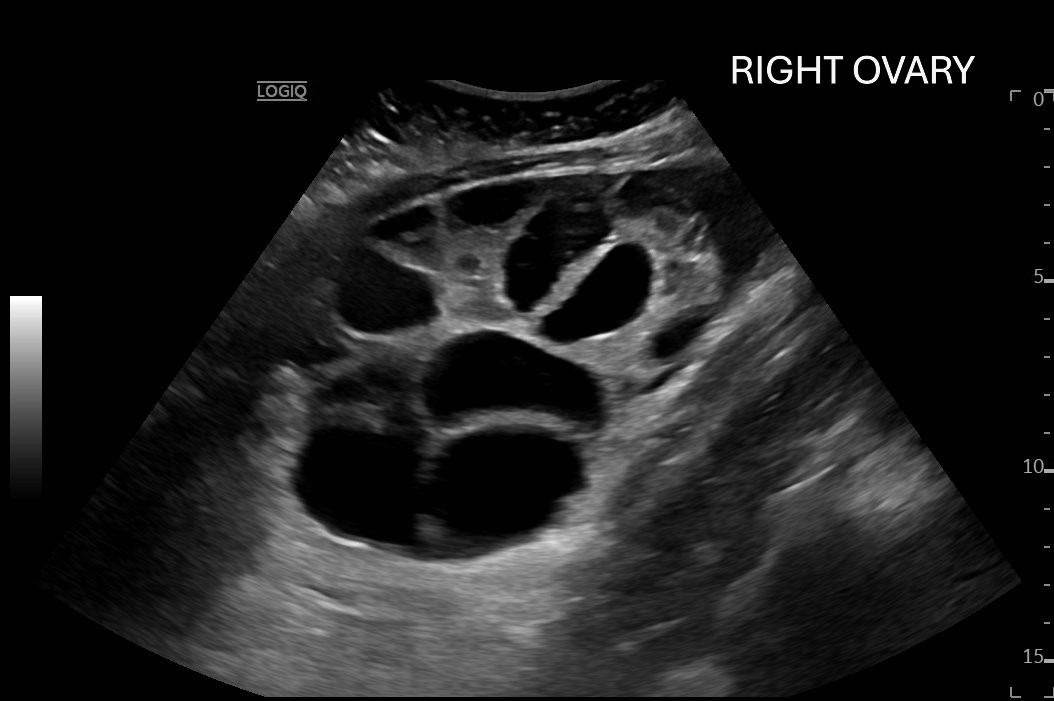

Ovarian hyperstimulation syndrome (OHSS) is a potentially life-threatening complication of assisted reproductive technology (ART). Here, we present the case report of a 30-year-old female undergoing infertility treatment who presented to the emergency department (ED) with nausea and vomiting, abdominal distention, and shortness of breath. On physical exam, she had notable ascites. Computed tomography (CT) of the abdomen and pelvis and pelvic ultrasound (US) revealed significant ascites and enlarged ovaries with multiple cysts. She was diagnosed with severe OHSS and admitted to obstetrics and gynecology (OBGYN) service for five days where she underwent intravenous (IV) hydration and paracentesis. This case report reviews the clinical presentation, categorization, management, and prevention of OHSS and provides examples of imaging findings consistent with the condition.